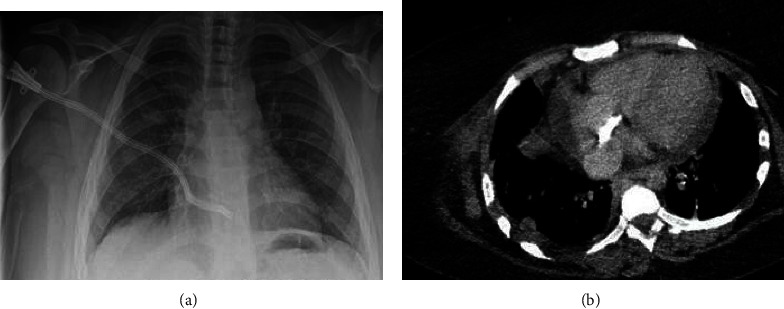

Introduction: Longer survival in dialysis led to a higher incidence of vascular access complications and failure. With the limited access to kidney transplantation programs and peritoneal dialysis, exhaustion of vascular access for hemodialysis is an increasingly common situation. Among the available options, atrial tunneled dialysis catheter (ATDC) has been reported as an effective vascular access in this population. Methodology. We report the experiences of two nephrology centers in Tunis with ATDC as an ultimate vascular access for dialysis. Case Reports. Two patients with exhausted vasculature underwent ATDC insertion in 2020 and 2022, respectively, as a vascular access of last resort. Both patients underwent CRBI, which resolved with favorable outcomes. One case was complicated by post-operative thrombosis and was successfully treated with thrombolysis. Both patients are currently on dialysis via their ATDC with a catheter patency of 29 months.

Conclusion: ATDC is a life-saving and safe vascular access in cases of depleted vasculature. Little more than 50 cases have been reported in the literature during the last 30 years. As the frequency of vasculature exhaustion is expected to increase, preservation of veinous access in patients at risk of chronic kidney disease have never been more crucial.